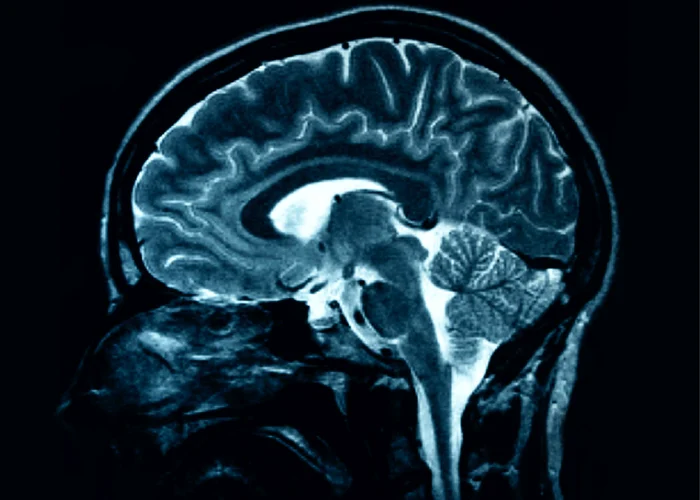

Sinestezia este un fenomen neurologic în urma căruia apare o asociație între senzații de natură diferită. S-a sugerat că unul din 2.000 de oameni ar avea sinestezie. Iată cum percep aceștia lumea.